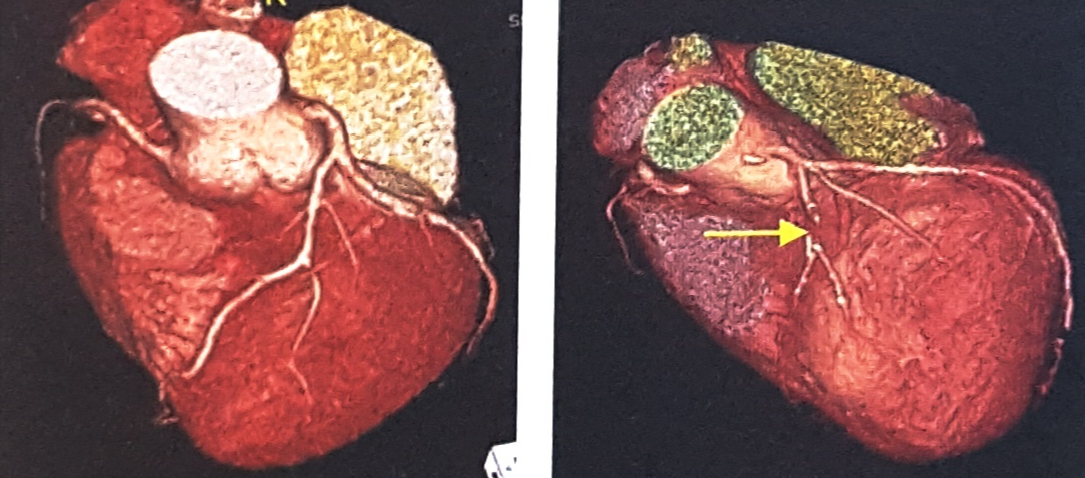

CT(Computed Tomography, 전산화단층촬영)검사는 신체의 일정 원하는 부위에서 단면을 깨끗한 2차원 영상으로 볼 수 있는 검사입니다. 촬영이 끝난 후 이러한 2차 단면영상을 컴퓨터를 이용하여 삼차원(3D)영상으로 재구성하면 동맥이 특별히 잘 보일 수 있도록 입체적인 영상도 얻을 수 있습니다.

CT촬영 종류에는 동맥 및 정맥 혈관 CT, 복부대동맥 CT, 심부정맥혈전 & 폐동맥 CT, 관상동맥 CT 등이 있습니다. 혈관질환의 정확한 검사 및 진단을 위해서는 혈관외과 전문의의 적절한 처방을 받아야 합니다.확인하고자 하는 대상에 따라서 촬영방법이 조금씩 차이가 있으나 기본적으로는 모두 같은 검사방법입니다.

심장자체에 위치하는 관상동맥